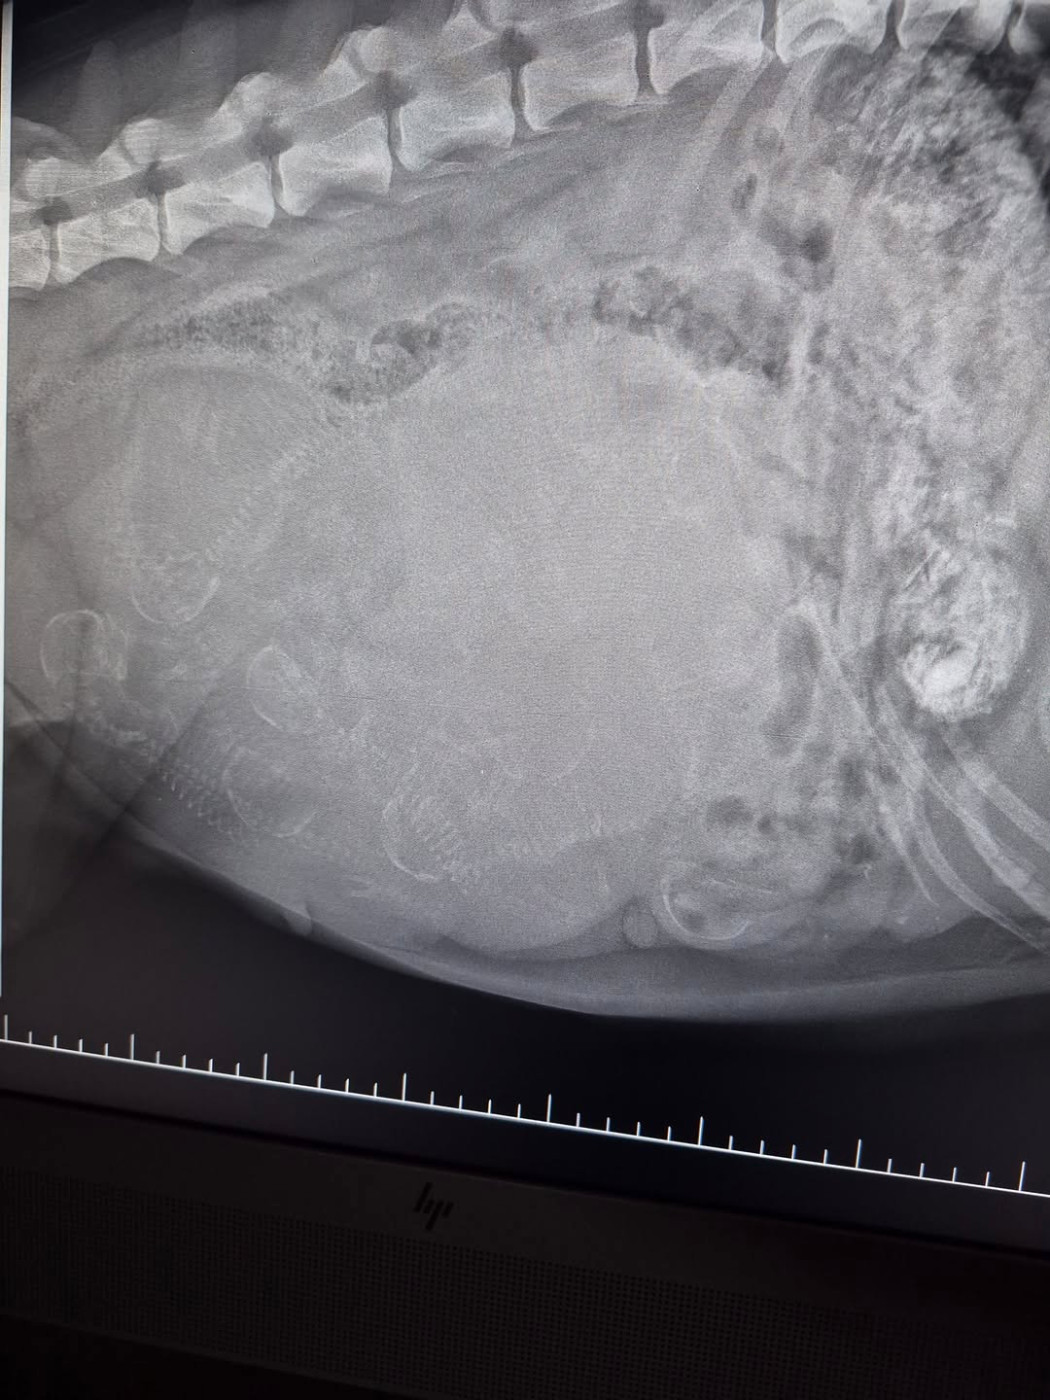

Notre petite belette Tina a donné naissance à 6 mâles et 2 femelles ! Le mariage a eu lieu fin novembre entre Tina de l'Empreinte des bergers et Roc'h ar hon Du mont de Sène confié par Chantal que nous remercions à nouveau pour ce superbe mâle ! Les chiots et la maman se portent bien ! Réservations ouvertes !Contactez nous sur desrubydejade@hotmail.com